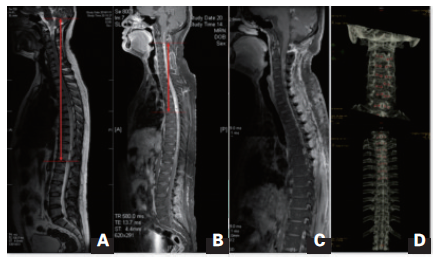

图 患者术前术后影响资料

MRI T2像显示肿瘤累及脑干和全部脊髓;B.增强扫描示肿瘤实体部分,强化明显,血供丰富;C.术后复查MRI示肿瘤 切除满意;D.术后CT复查提示所有椎板复位满意。